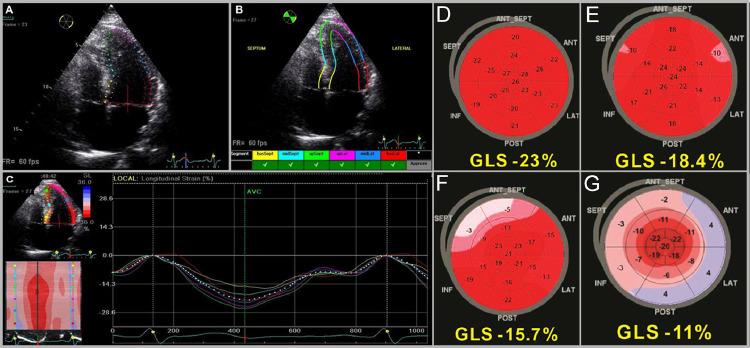

Speckle tracking echocardiography as a new diagnostic tool for an assessment of cardiovascular disease in rheumatic patients.斑点追踪超声心动图作为一种新的诊断工具,用于评估风湿患者的心血管疾病。

Prog Cardiovasc Dis. 2020 May-Jun;63(3):327-340. doi: 10.1016/j.pcad.2020.03.005. Epub 2020 Mar 20.